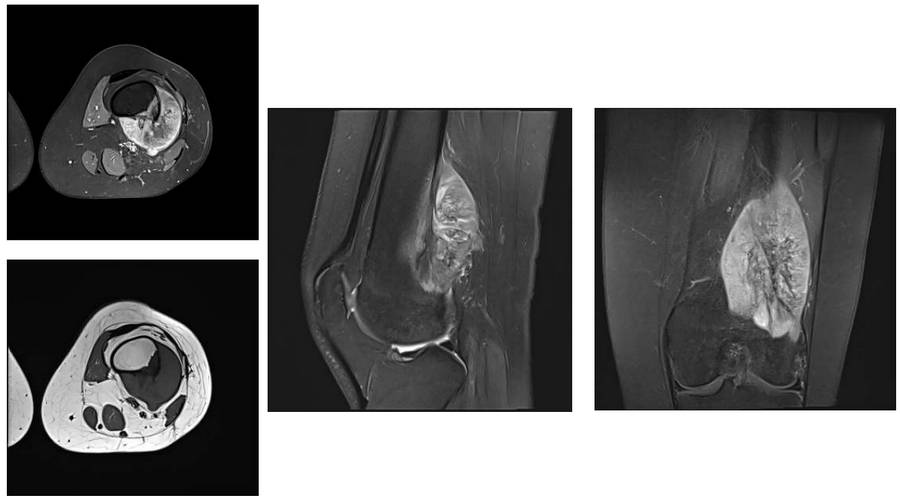

Before the surgery: The MRI shows tumor tissue adjacent to the vascular nerve bundle in the same location.